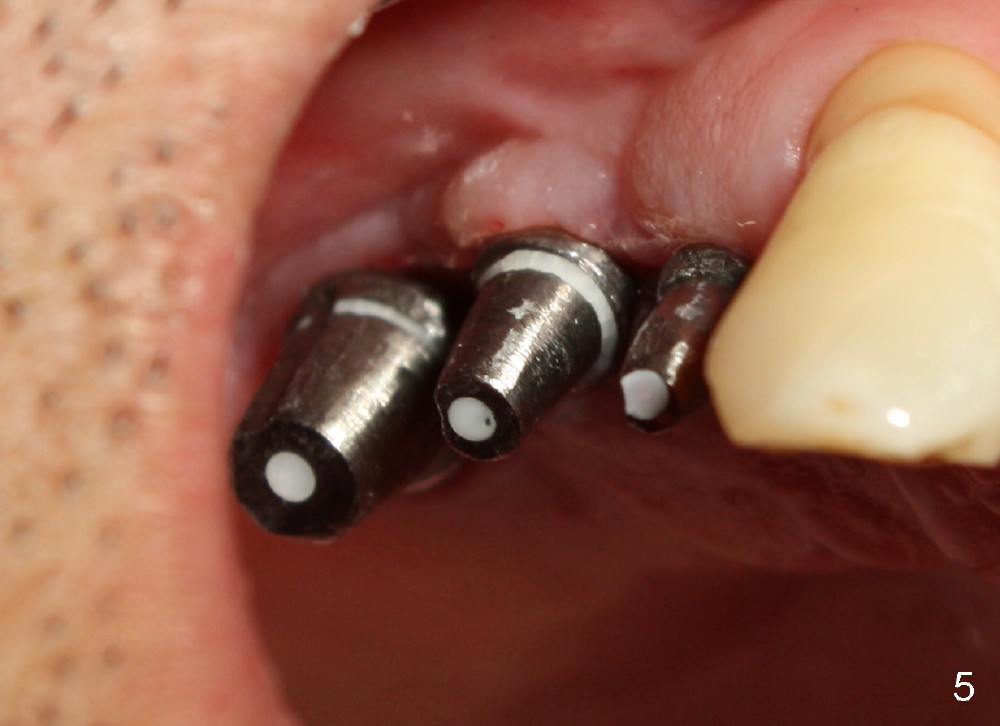

Implants at the site of #3 and 5 were placed for Kent a month earlier. Immediately before placing a third one in between, something had been done for the first two implants in preparation for guidance. Can you guess what that is?

In fact, healing screws had been removed (Fig.1). There is space inside the well of the implant #5 and less obvious in that of #3 (because its wall is thicker). When implants tilt, the opening of the wells is visible (Fig.2-4).

A post guide (Fig.2: P) was inserted to the well of #5 implant as a guide for #4 pilot drill and continually for a drill with larger diameter (Fig. 3 D). Implant placement was a breeze (Fig.4). Two months later, three of the straight abutments (0 degree) were also parallel to each other.